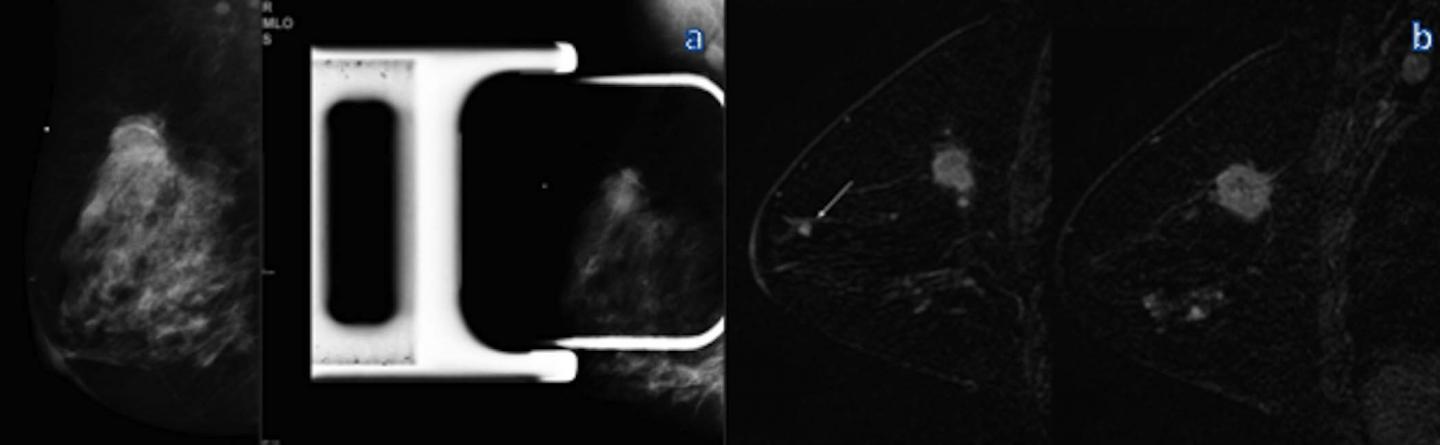

image: Mammography and MR imaging in a 46-year-old woman with a palpable mass in the right breast. A: Mediolateral oblique (left) and spot compression (right) mammograms in the right breast show a mass in the upper-outer quadrant. B: Sagittal dynamic breast MR images in the right breast show an en-hancing mass with speculated, or spiky, margins in the right upper outer quadrant, an additional focus near the nipple (DCIS), and nonmass enhancement in the inferior quadrants (DCIS). The additional lesions were not visible at US and were biopsied with MR imaging guidance. view more

Credit: Radiological Society of North America